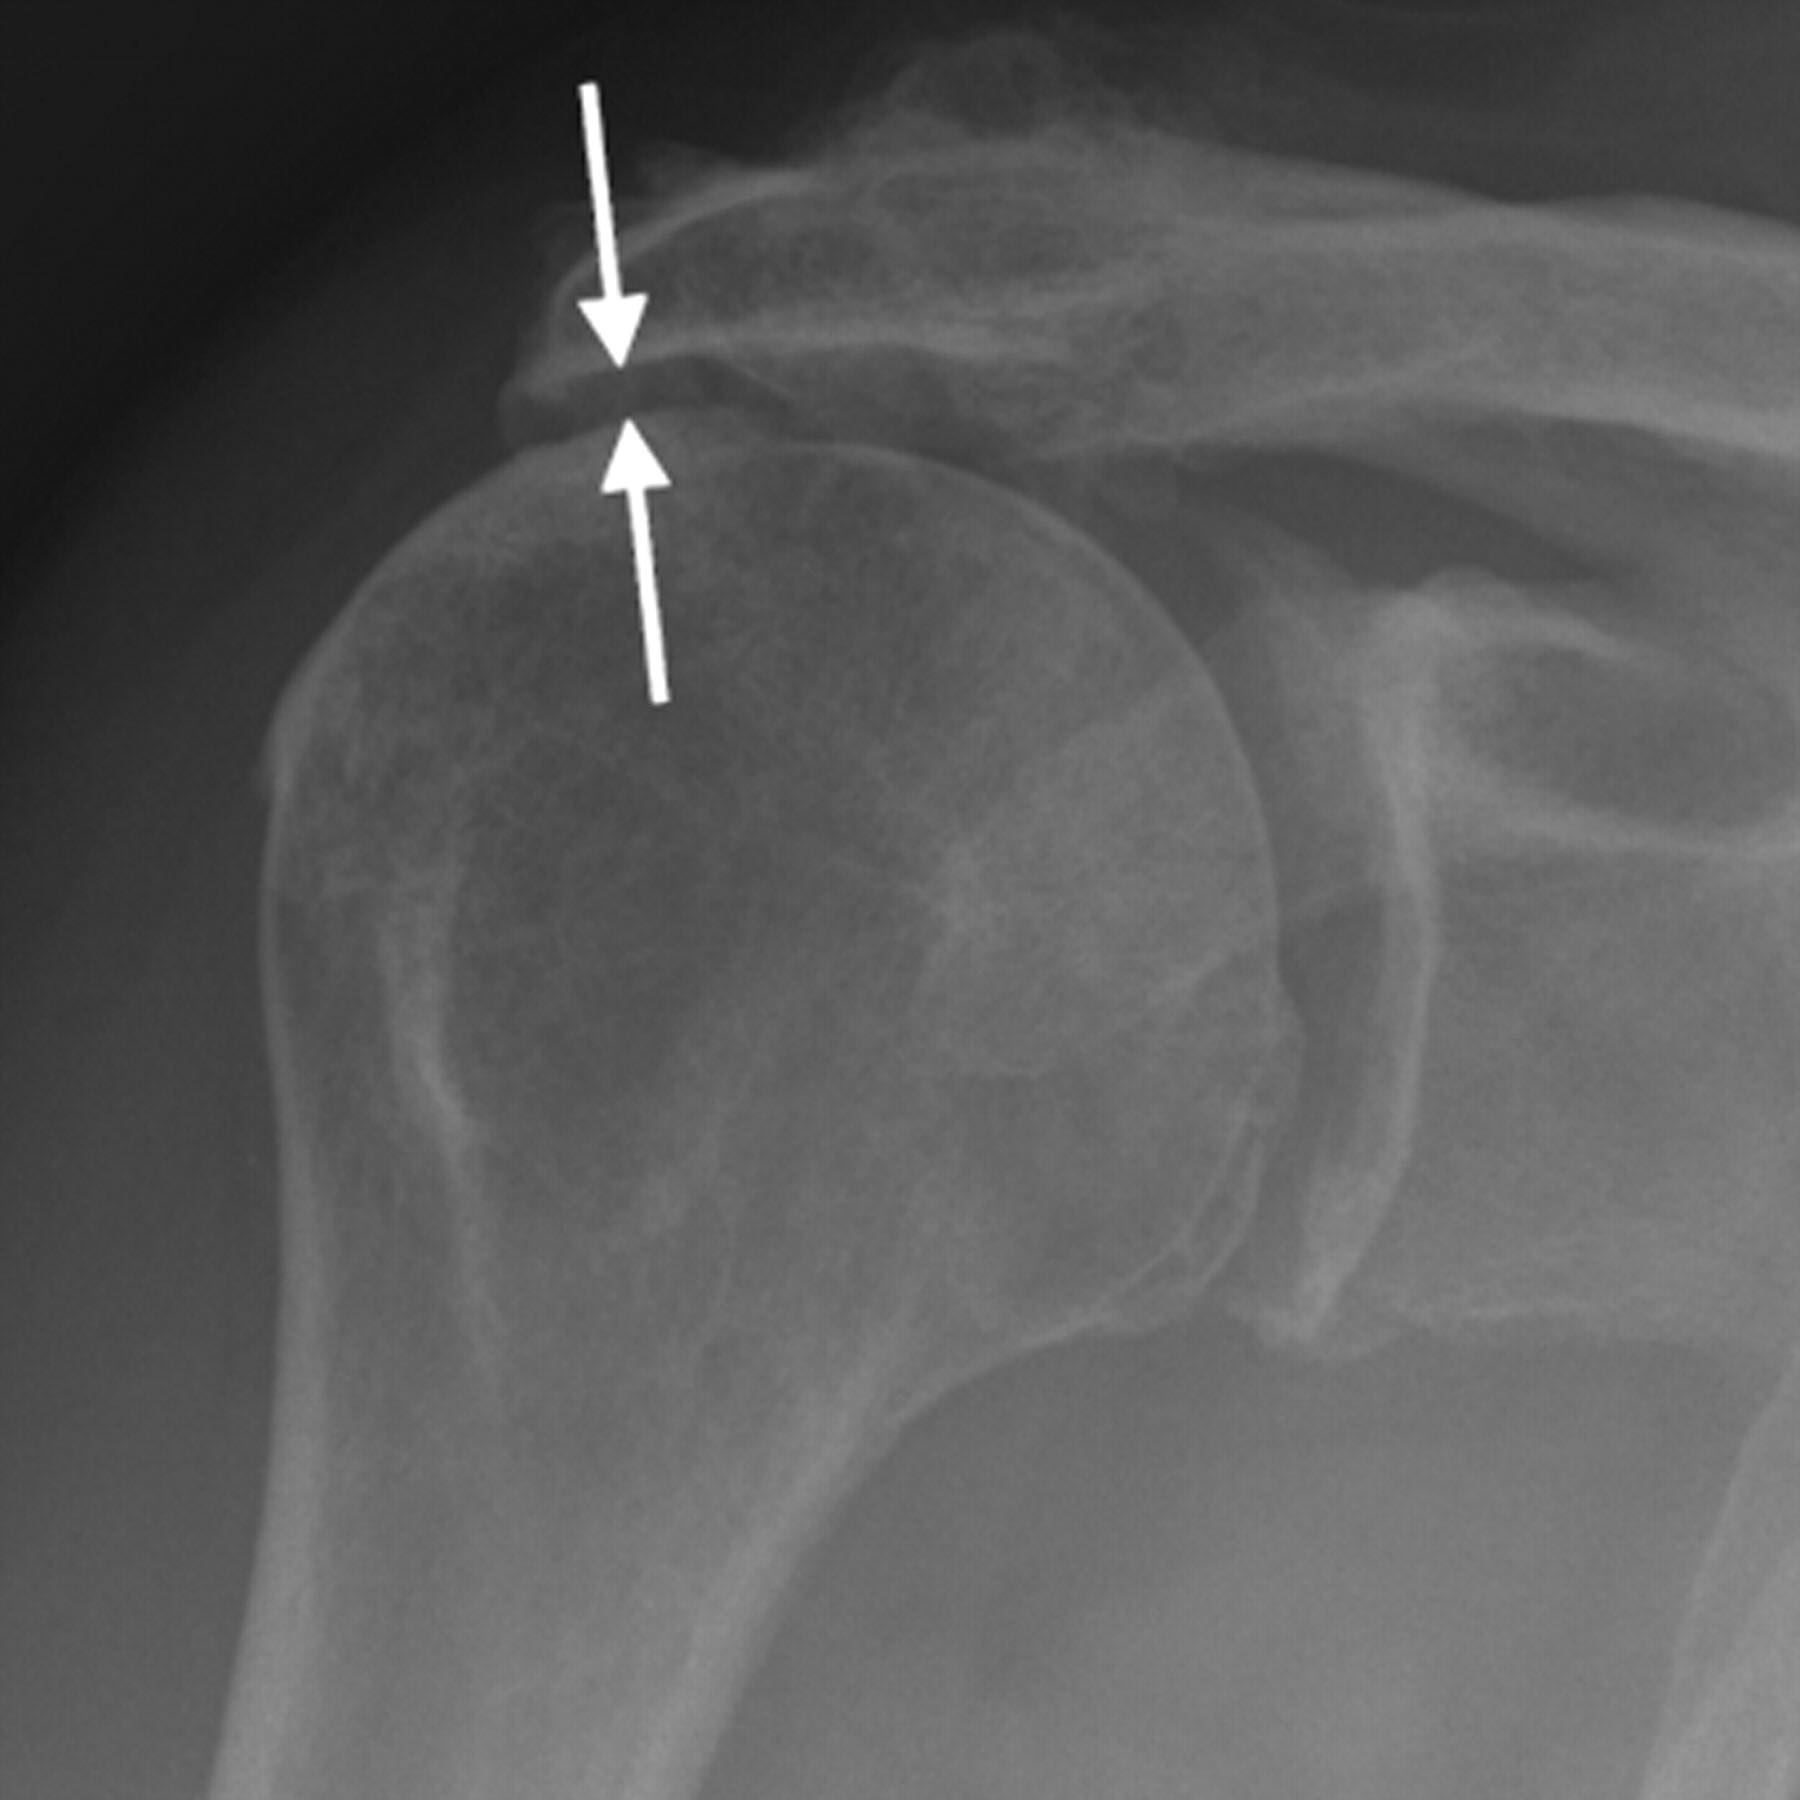

Pas de diminution de l'espace sous-acromial.

Respect de l'articulation acromio-claviculaire.

Intégrité de l'interligne articulaire gléno-huméral.

Pas de calcification en projection des tendons de la coiffe des rotateurs.

Pas de lésion suspecte dans les structures osseuses et les parties molles.

angle CSA < 30° arthrose / > 35° rupture coiffe

distance acromio-humérale < 7 mm rupture coiffe